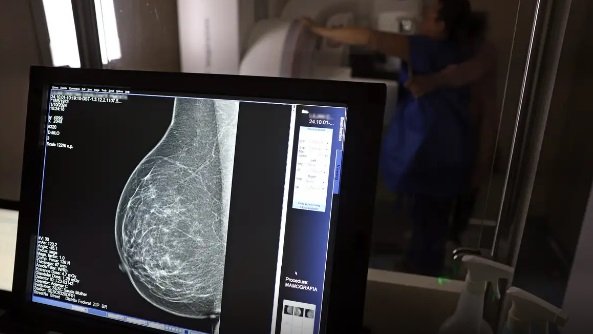

Ministério da Saúde passa a recomendar mamografia a partir dos 40 anos

O Ministério da Saúde passou a recomendar o acesso a mamografia, via Sistema Único de Saúde (SUS), para mulheres de 40 a 49 anos – mesmo que não haja sinais ou sintomas de câncer de mama. De acordo com a pasta, a faixa etária concentra 23% dos casos da doença, e a detecção precoce aumenta as chances de cura. Até então, a orientação era que o exame fosse feito a partir dos 50 anos. A medida faz parte de um conjunto de ações anunciadas nesta terça-feira (23) voltado para a melhoria do diagnóstico e da assistência. A recomendação para mulheres a partir dos 40 anos é que o exame seja feito sob demanda, em decisão conjunta com o profissional de saúde. “A paciente deve ser orientada sobre os benefícios e desvantagens de fazer o rastreamento. Mulheres nesta idade tinham dificuldade com o exame na rede pública de saúde por conta da avaliação de histórico familiar ou necessidade de já apresentar sintomas”, informou o ministério em nota. As mamografias via SUS em pacientes com menos de 50 anos, de acordo com a pasta, representam 30% do total, o equivalente a mais de 1 milhão apenas no ano de 2024. Rastreamento ativo Outra medida anunciada é a ampliação da faixa etária para o rastreamento ativo – quando a mamografia é solicitada de forma preventiva a cada dois anos. A idade limite, até então, era 69 anos. Agora, passa a ser 74 anos. Dados do ministério revelam que quase 60% dos casos de câncer de mama estão concentrados entre 50 e 74 anos. “A ampliação do acesso à mamografia aproxima o Brasil de práticas internacionais, como as adotadas na Austrália, e reforça o compromisso em garantir diagnóstico precoce e cuidado integral às mulheres brasileiras. O câncer de mama é o mais comum e o que mais mata mulheres, com 37 mil casos por ano”, reforçou a pasta. Os números mostram que, em 2024, cerca de 4 milhões de mamografias para rastreamento e 376,7 mil exames diagnósticos foram realizados no SUS.